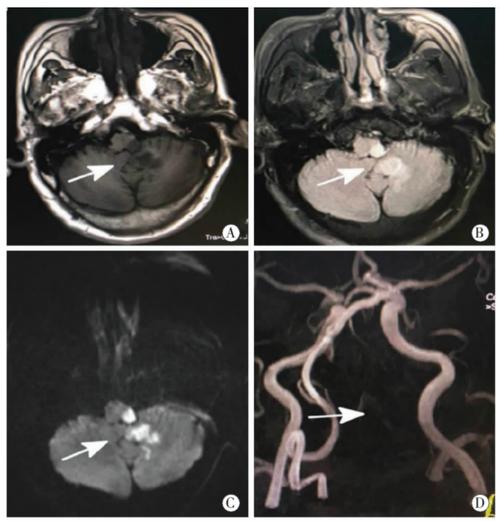

明确病因:血管堵在哪里?堵住了多少?

这是MRA最核心的价值,医生需要知道:

- 责任血管是哪一根? 是大脑中动脉、颈内动脉还是其他血管?这决定了梗死的区域和治疗方案。

- 堵塞的程度如何? 是轻度狭窄、重度狭窄,还是完全闭塞?

- 堵塞的性质是什么? 是局部血栓形成,还是远处的栓子脱落造成的栓塞?

示例:

- MRA显示右侧大脑中动脉M1段重度狭窄或闭塞,高度怀疑该血管是本次脑梗的“罪魁祸首”。

- MRA显示颈内动脉起始部有巨大斑块,可能是栓子的来源地。